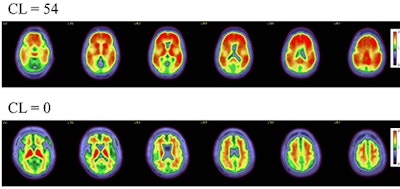

Axial color scales images of two brains show examples of an amyloid positive scan with a higher centiloid (CL) number and more red colors compared to a normal scan with normal background binding of the amyloid tracer signifying no amyloid plaques.Image and caption courtesy of RSNA.